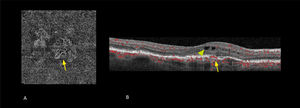

DiagnósticoGracias al progreso tecnológico, en los últimos años se han introducido nuevas herramientas de evaluación macular no invasivas que permiten obtener imágenes de alta definición del fondo de ojo de manera rápida. Estas técnicas se utilizan de forma rutinaria en la práctica clínica. De manera destacada, la tomografía óptica de coherencia de alta resolución (OCT dominio espectral y swept source) y la tomografía óptica de coherencia de alta resolución asociada a angiografía (OCT-A)7 (figura 6) han brindado un mayor conocimiento sobre la enfermedad y sus distintas etapas evolutivas.

OCT-A (angiografía de retina por tomografía de coherencia óptica) en fase a nivel del epitelio pigmentario (A) y asociado a OCT estructural (B)

Las imágenes muestran que la membrana neovascular coroidea ha penetrado por debajo del epitelio pigmentario (flecha) y edema intraretinal (punta de flecha).